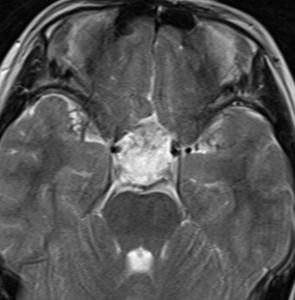

小脳類皮のう胞

偶然発見された女の子のものです。左のCTで石灰化があります。右の拡散強調画像 DWI で白く高信号に描出されるのが特徴です。手術では腫瘍内部に毛髪がたくさんありました。後下小脳動脈に強く癒着していて,脳軟膜からの剥離もできませんでしたが,完全摘出しました。無症状でも”完全”摘出 complete removal するべきです。